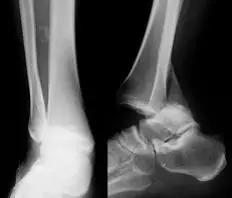

6. Pilon 骨折

涉及负重关节面(胫距关节面)与胫骨远侧干骺端的骨折。其典型特征是干骺端存在不同程度的压缩、干骺端的压缩粉碎性骨折不稳定、原发性关节软骨损伤以及永久性关节面不平整导致预后不良。

pilon 骨折正位片

pilon 骨折侧位片

pilon 骨折三维 CT 表现